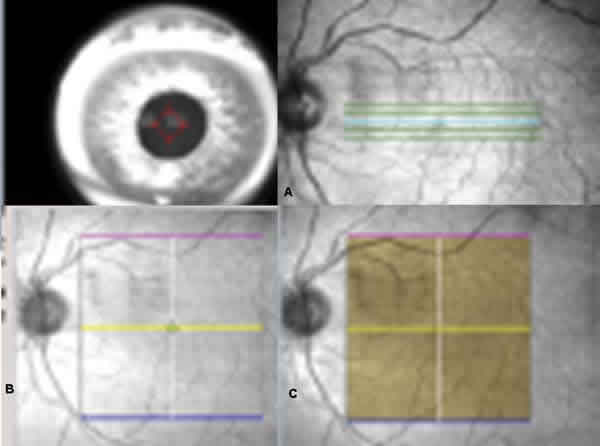

Zeiss produce y distribuye el Stratus, un tomógrafo de coherencia óptica que usa un haz de luz que escanea rápidamente el ojo y nos muestra cortes seccionales de la retina. Tras el éxito cosechado por el Stratus, ha lanzado al mercado el Cirrus™ HD-OCT, un instrumento que incorpora aspectos del Stratus. Presenta un haz de corte muy similar al Stratus pero con una resolución axial mejorada y una mayor velocidad de escaneo (50 veces más rápido o superior) que permiten explorar un área mayor de retina. Mientras que el Stratus adquiere los datos del cálculo de espesor recogiendo 256 A-scan a lo largo de 6 líneas B-scan que pasan a través del centro de la fóvea, el Cirrus adquiere los mismos datos recogiendo 200 A-scans de 200 B-scan lineales que están distribuidos en un cuadro de 6 mm del centro de la fóvea. Así presenta significativamente muchos más puntos y consigue explorar zonas que el Stratus no podía valorar por tratase solamente de 6 líneas. Se trata de un compacto OCT en el que está incluido en el mismo el monitor de color de 15" y el ordenador (fig. 4). Es un OCT de última generación, no midriático que está basado en el dominio espectral con un sistema de OCT de alta definición. Se trata de un OCT que utiliza como fuente de luz un diodo superluminiscente con una longitud de onda de 840 nm con una velocidad de escaneo de 27.000 cortes axiales por segundo. La longitud axial y horizontal de resolución es de 5 y 15 mm, respectivamente. Los patrones de escaneo que realiza son el Macular Cube 200 x 200 (200 líneas horizontales que constan de 200 cortes axiales), Macular Cube 512 x 128 (128 líneas horizontales que constan de 512 cortes axiales) y el 5 Line Raster 4096 cortes axiales por B-scan (fig. 5). El diámetro pupilar mínimo necesario es de 2 mm pero el óptimo es a partir de 3 mm. La visión del campo es de 36º x 30º. El rango de ajuste de foco es de -20D a +20D.

Fig. 5: Macular Cube 200 x 200 (200 líneas horizontales que constan de 200

cortes axiales), Macular Cube 512 x 128 (128 líneas horizontales que constan de

512 cortes axiales) (B y C) y el 5 Line Raster 4096 cortes axiales por B-scan

(A).

El Stratus adquiere los datos del espesor recogiendo 256 A-scans a lo largo de 6 líneas de B-scan que pasan a través del centro de la fóvea. El Cirrus los toma analizando 200 A-scan de 200 líneas de B-scan que están distribuidas en 6 mm de un cuadrado centrado en la fóvea. El Cirrus presenta muchos más puntos, y la distribución de dichos puntos está más repartida en cada subcampos. El Stratus se centra más en el centro de la fóvea pero no puede valorar correctamente regiones de la anatomía que se pierden por el escaner al no pasar por ellos (fig. 6).

Fig. 6: Escaneo completo que presenta el Cirrus en un cubo de 200 x 200 frente a

las 6 líneas radiales del Stratus.

Paciente previamente diagnosticada de DMAE atrófica en ambos ojos que acude a nuestra consulta para valoración presentando una agudeza visual de 0,05 en el ojo derecho y de 0,86 en ojos izquierdo. En el fondo de ojo se observa maculopatía atrófica en ambos ojos con restos de sangre en el ojo derecho perifoveal. En la imagen OCT se observa la clara diferencia en definición de imagen con respecto al fluido subretiniano del Stratus (fig. 7) en comparación con el Cirrus (fig. 8) y la escala de colores utilizada por éste (fig. 9).

Fig. 9: Mapa de espesores del cuadrado escaneado, por código de colores del

Cirrus.